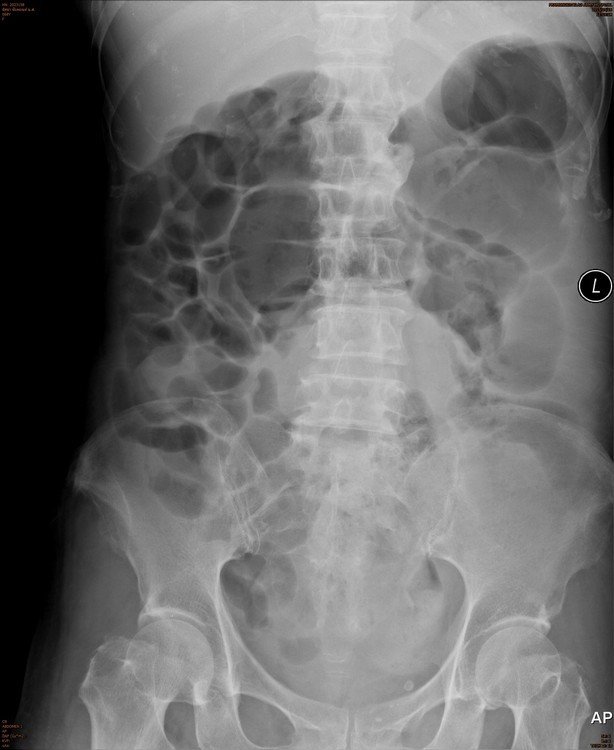

Answer : B. Abdominal/Pelvic mass

• Occasionally masses of the pelvis are visible on an abdominal X-ray.

• If large, masses of the pelvis may extend into the abdomen and displace bowel.

• Investigation with ultrasound and/or CT is required for assessment of a suspected abdominal mass.

Key points : Pelvic masses can displace bowel upwards